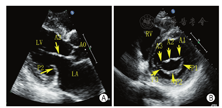

超声心动图在MR介入术中起着不可或缺的作用,下面以目前最为成熟的经导管二尖瓣夹合术MitralClip为例,阐述MR介入术中的超声评价。MitralClip是在TEE实时监测和引导下的操作,所有的导管操作由TEE监测和引导[16]。TEE首先引导房间隔穿刺,使得房间隔穿刺点距二尖瓣瓣环平面的高度3.5~4 cm(图11)。之后,TEE引导输送系统进入左心房并调弯、顶端垂直指向二尖瓣口。接着,TEE引导夹合器在二尖瓣上方定位,夹合器进入左心室,引导夹合器捕获和夹合瓣膜。夹合器捕获瓣膜位置,应该位于彩色多普勒显示反流束最大处。在整个手术过程中,两个超声切面非常重要,为手术的工作切面(X-plane双切面),包括三腔切面(左心室长轴切面)及二尖瓣交界处两腔切面(图12),前者可以显示二尖瓣A2、P2的位置,捕获瓣膜前二尖瓣夹合器应该在这个切面显示为"V"形,此时瓣夹合器臂与二尖瓣开放线垂直,分别位于A2、P2的位置,在该切面通过调整夹合器位置可使得夹合器更靠近前叶或后叶;后者显示P1,A2,P3,捕获瓣膜前二尖瓣夹合器在该平面应该为直线形,在该切面通过调整夹合器位置可使得夹合器更靠近内交界(3)或外交界(1)。另外一个工作切面为三维超声心动图的"二尖瓣外科视野",可以整体观察夹合器的位置、臂指向的方向(图13)。目前有限经验显示,经心尖二尖瓣夹合术(ValveClamp)术中超声指导和MitralClip总体上类似,但仍有部分差异,其超声规范尚在探索中。